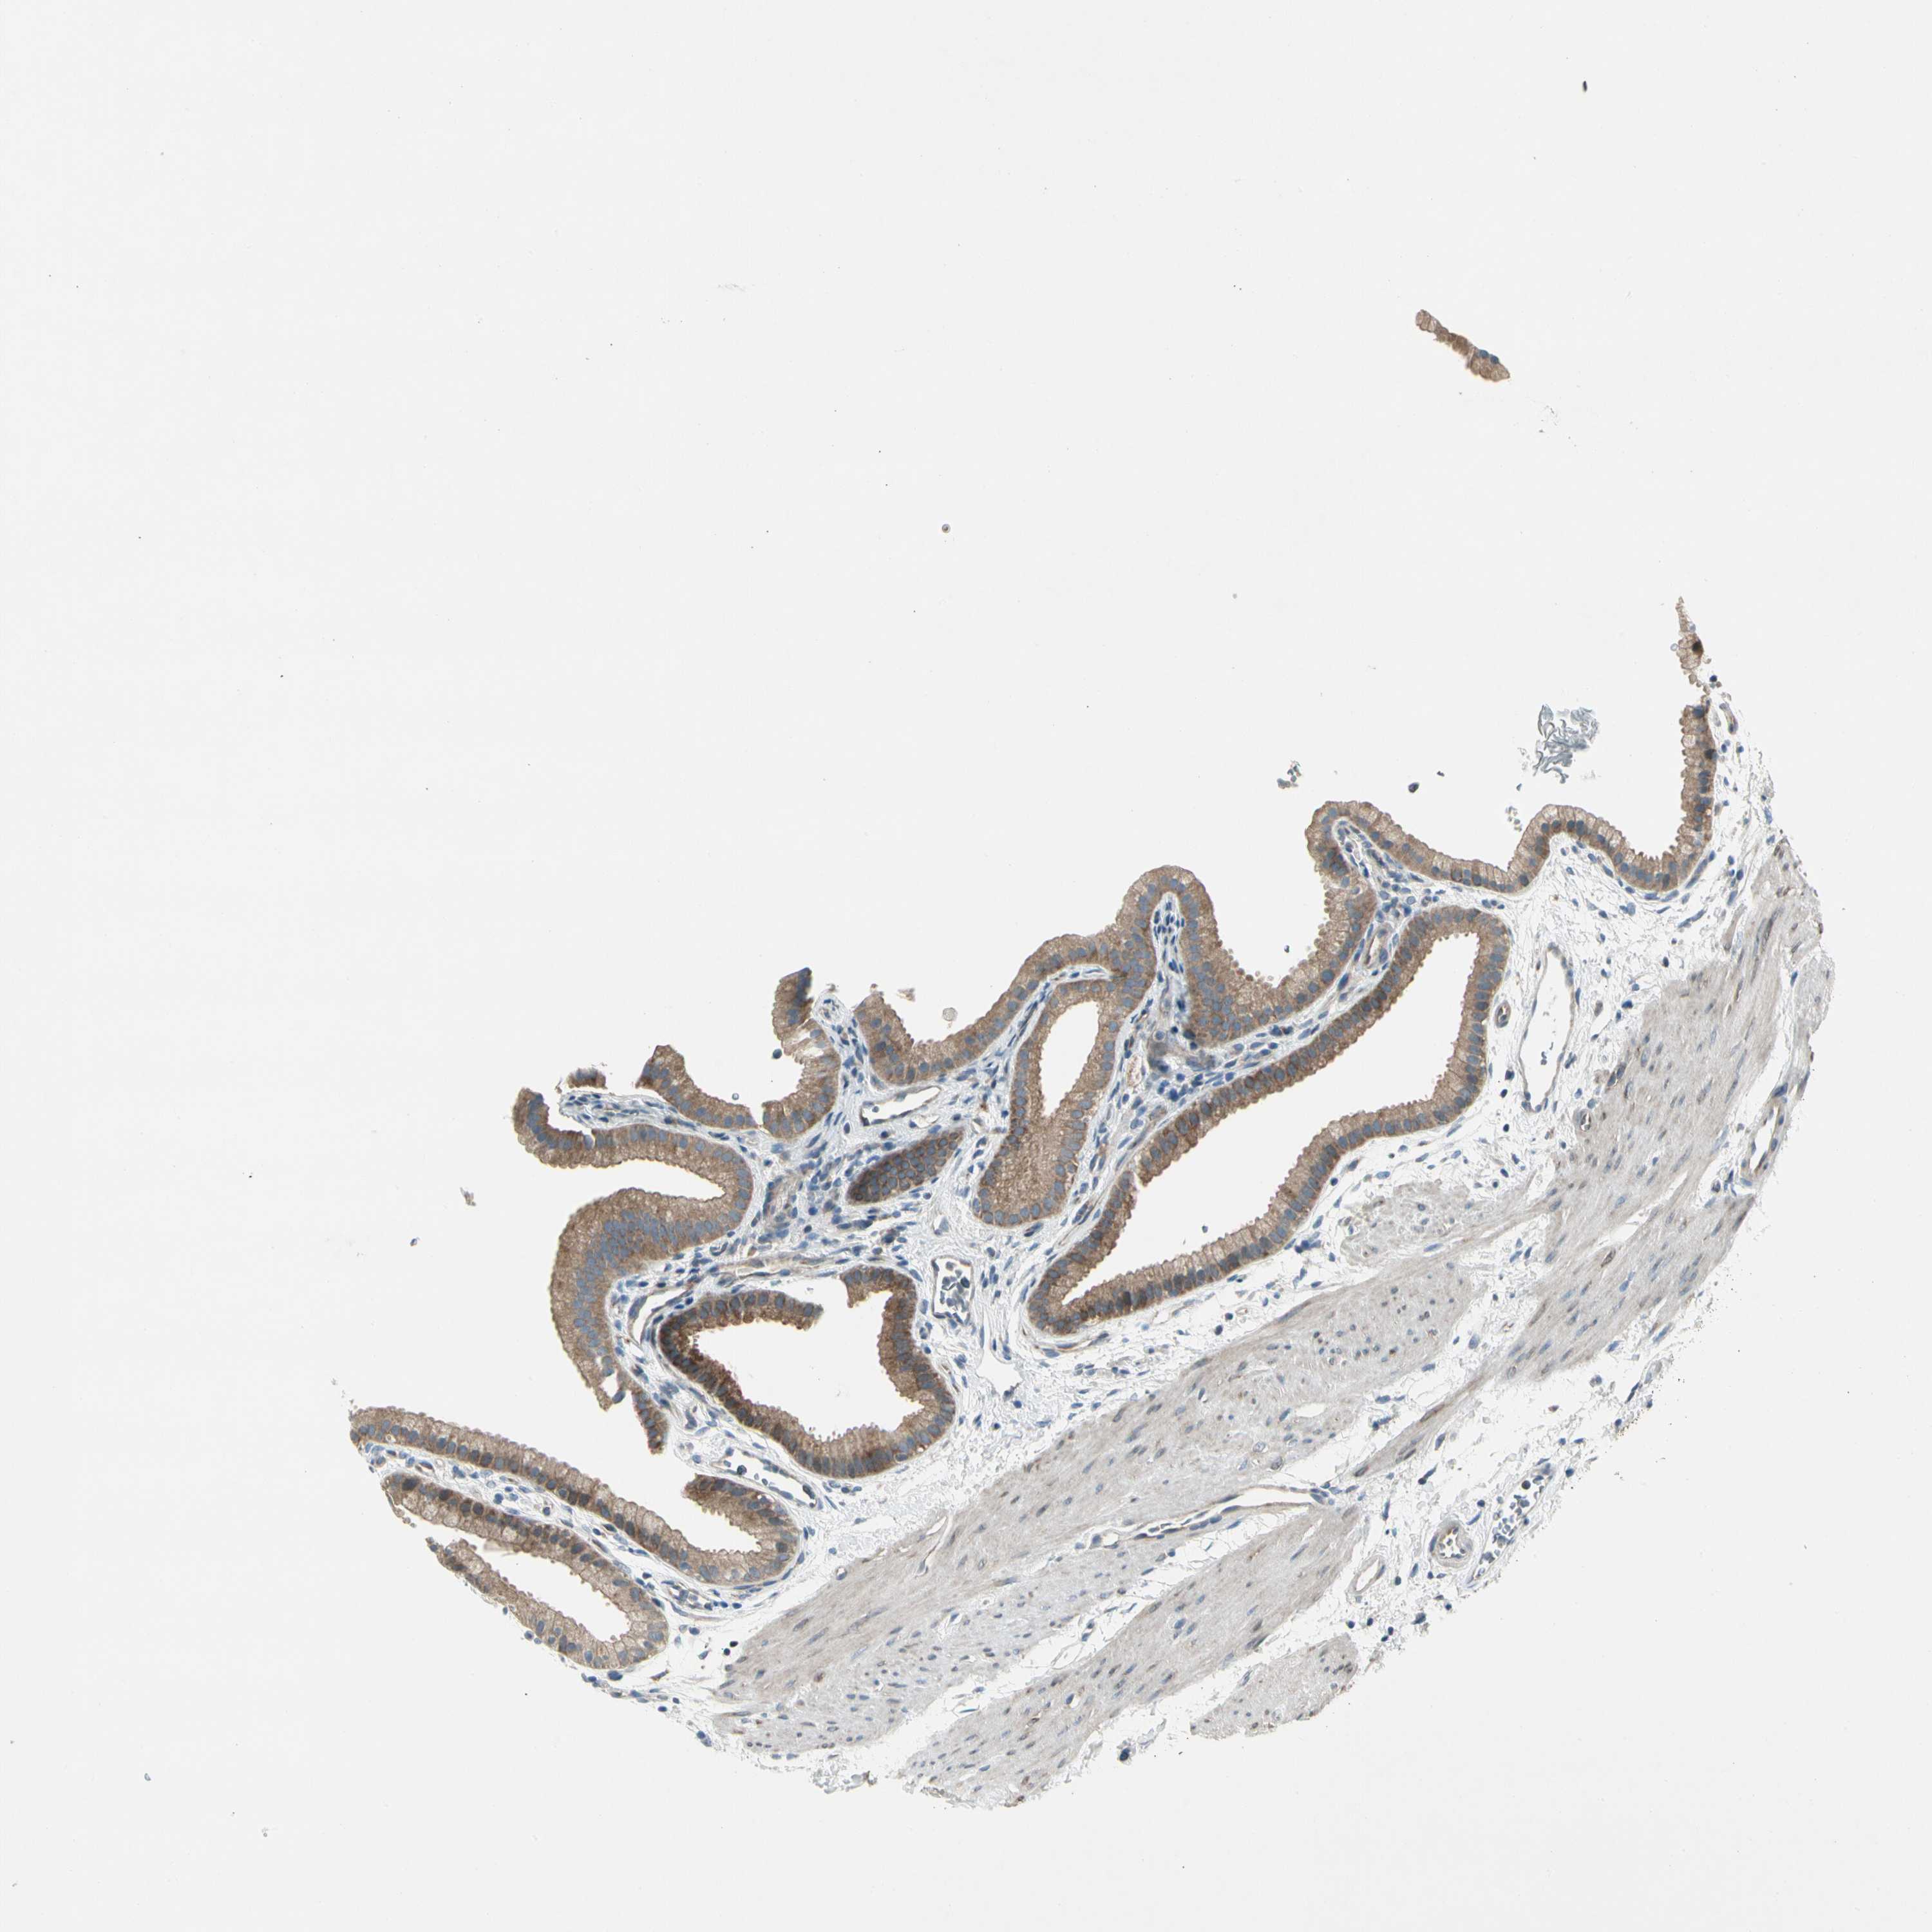

PANK2